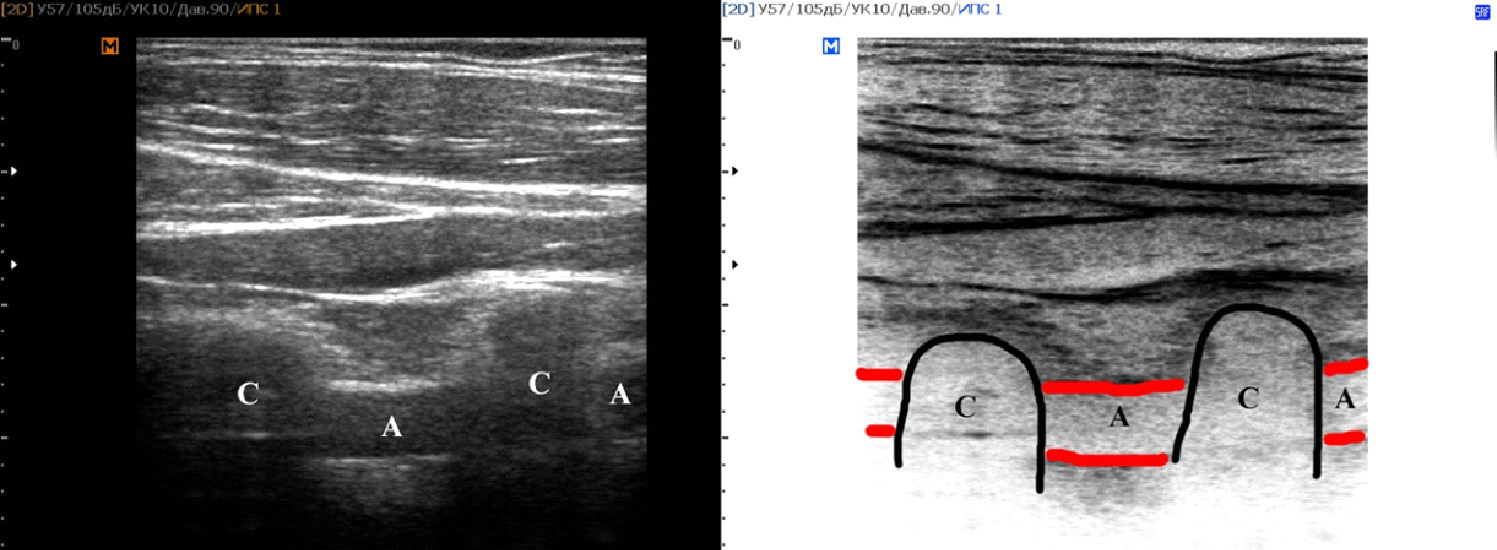

В результате наблюдения без учета стороны визуализации было проанализировано 504 сосудистых комплекса, включавших позвоночные артерии и сопровождающие их вены. Среди женщин было выявлено 146 случаев прямолинейного хода сосудов и 202 случая непрямолинейного хода сосудов (рисунок 1). У мужчин было определено 70 сосудистых комплексов (рисунок 2) с прямолинейным ходом и 86 с непрямолинейным. При оценке статистической значимости данных для всех значений были получены результаты p<0,005 по Стьюденту.

Рисунок 1. Пациент №245 Б, женщина 65 лет. Пример визуализации непрямолинейного хода сосудов на уровне V2 сегмента позвоночных артерий (SonoAce R7, линейный трансдьюсер).